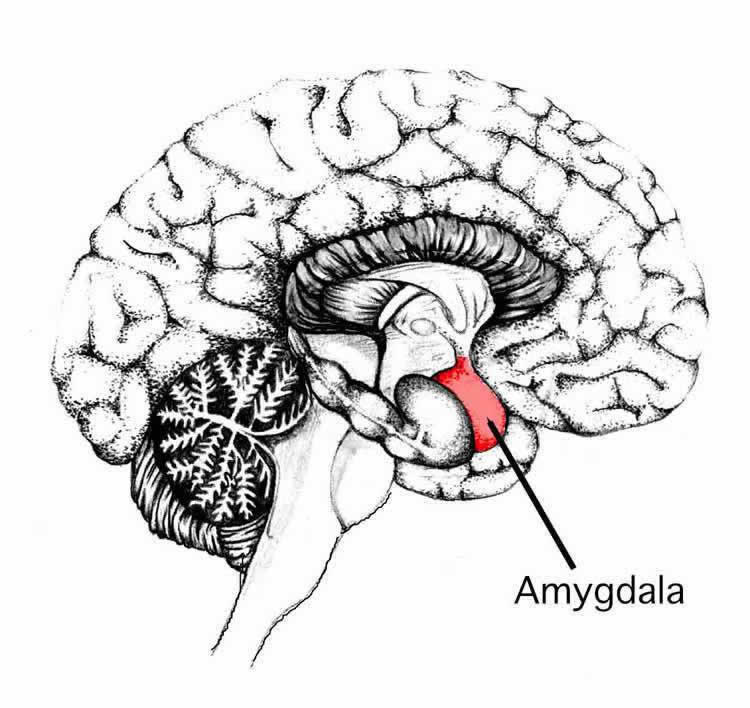

Amygdala: What It Is and What It Controls

Know Your Brain: Amygdala

Damage to the Amygdala: Functions, Symptoms, & Treatments

Amygdala Function and Location

Amygdala's Location and Function

Amygdala: Anatomy, Location, and Function

Amygdala | Facts, Position In Brain, Summary & Function

Schematic drawing illustrating the location of the amygdala and